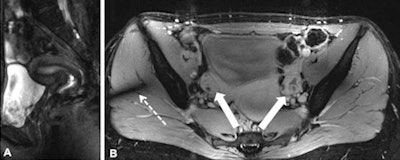

The researchers found 2D FLASH MRI offered the best overall image quality (mean contrast-enhanced 4.9) and highest tissue contrast (mean contrast-enhanced 4.7), while T2-weighted TSE imaging provided moderate to high conspicuity of the uterine zonal anatomy, with mean scores ranging from 3.5 for endometrium to 4.65 for myometrium. Overall image impairment was rated strongest for T2-weighted MRI (2.9) and least for 2D FLASH MRI (mean 4.2).

T1-weighted fat-saturated 2D FLASH MRI resulted in good image quality, providing excellent tissue contrast and high spatial resolution and revealed the potential for ultrahigh-field perfusion MRI, enabling further evaluation of possible pelvic pathologies.

T2-weighted TSE MRI showed high-quality delineation of specific uterine anatomy with comparable contrast to lower field strengths, yet remained challenging because of limitations associated with ultrahigh magnetic field strength, they wrote.